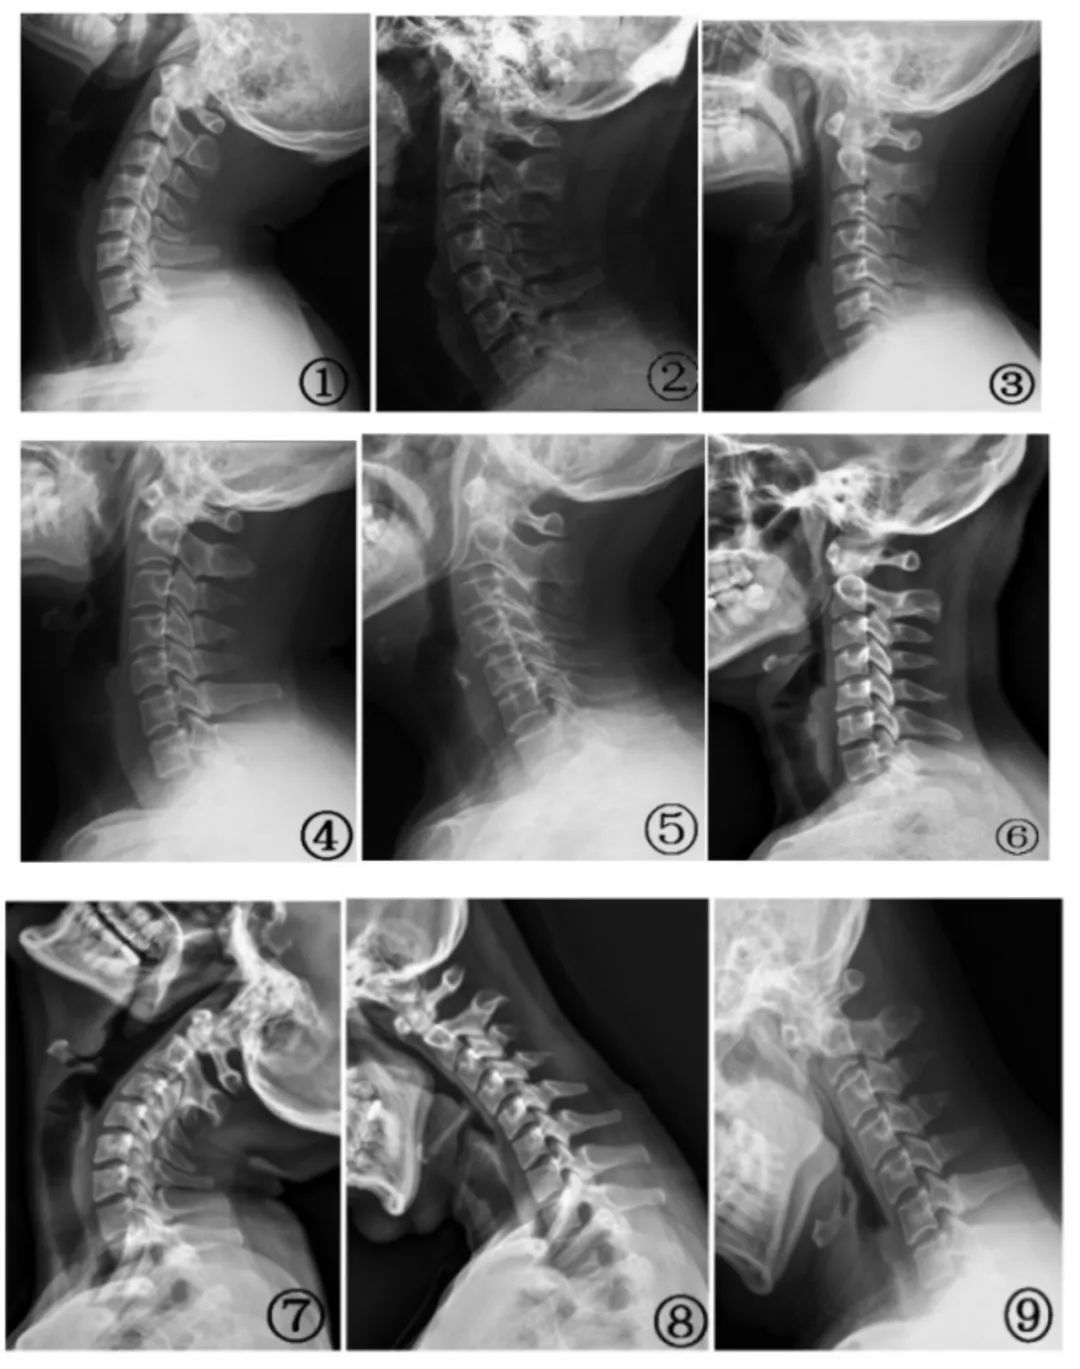

圖① 頸椎側位片;圖② 曲度增加;圖③ 曲度變直;圖④ 曲度變小;圖⑤ 弓頂移位;圖⑥ 輕度反弓;圖⑦ 過伸位頸 4、5 椎體水平位移; 圖⑧ 過曲位中段椎體角位移;圖⑨ 過曲位中下段椎體角位移和頸 5、6 水平位移。